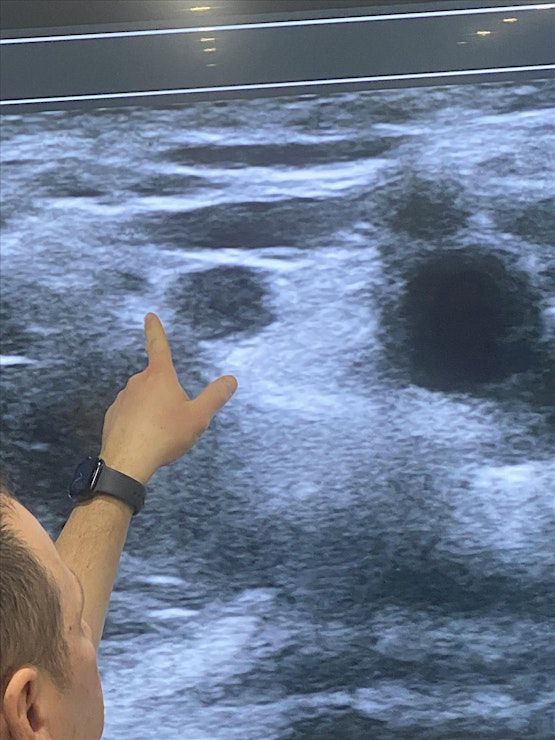

This 1 day intensive workshop has been developed for both novices and advanced pain physicians providers who would like to either learn the basics or further advance their skills in ultrasound guided pain procedures and regional anesthesia. Participants will have up to 6 hours of hands on ultrasound scanning on live models and lecture to learn and identify different sono‐anatomy. At the end of the workshop, you will be expected to have gained thorough knowledge and immense confidence in the use of ultrasound for pain procedures

• Identify normal sono‐anatomy and aberrations

13:00 -15:00 Hands on Scanning: Live Models

Scanning Live Models for Ultrasound Guided Joint Injections & Nerve Blocks